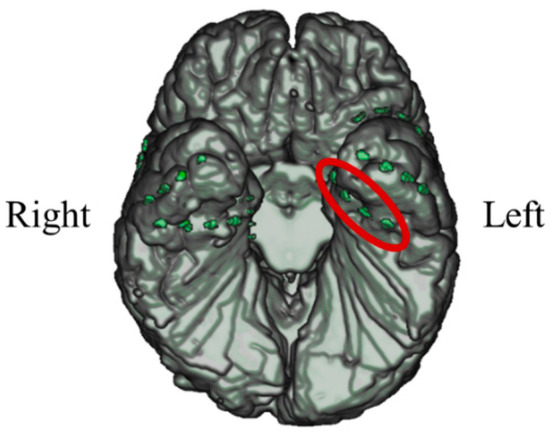

In P03, subdural electrodes (Unique Medical, Tokyo, Japan) were implanted in the left MTL. Four platinum electrodes (3.0 mm in diameter) were laterally placed at 10 mm intervals (centre to centre) along the left parahippocampal gyrus, and intracranial EEG was measured and used for NF (Figure 20). A reference electrode placed on the dural side of the left temporoparietal lobe was used for P03.